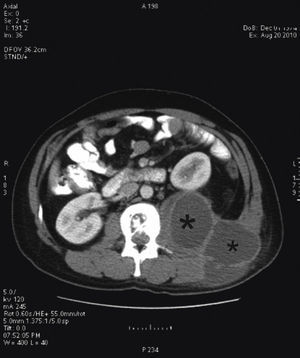

Tras el ingreso se solicitó un estudio con TC, diagnosticándose lesión lítica de borde escleroso en cuerpos vertebrales L1 y L2, centrada en el disco, compatible con espondilodiscitis. Se acompañaba de un gran absceso en el psoas y musculatura lumbar izquierda, que desplazaba hacia delante el riñón izquierdo y se extendía a tejido subcutáneo (figs. 2 y 3). La punción guiada por TC permitió retirar 440 cc de líquido purulento y aspecto caseoso. La baciloscopia de este encontró positividad con 10 bacilos/campo y el cultivo demostró crecimiento de Mycobacterium tuberculosis complex.

El interés de este caso recae en la presentación inespecífica y larvada del cuadro clínico a pesar de la afectación tan notable que se aprecia en las imágenes de la TC. Además, demuestra la utilidad de tal estudio en el diagnóstico para un tratamiento oportuno, para demostrar una afectación tan notable como la de la imagen.